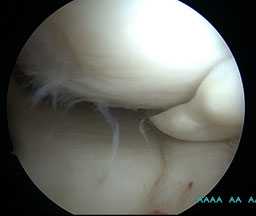

Разрыв внутреннего мениска по типу «ручки лейки» с блоком коленного сустава (невозможность полностью разогнуть коленный сустав). На фотографии хорошо виден крупный фрагмент мениска плотно зажатый между суставными поверхностями бедренной и большеберцовой кости.